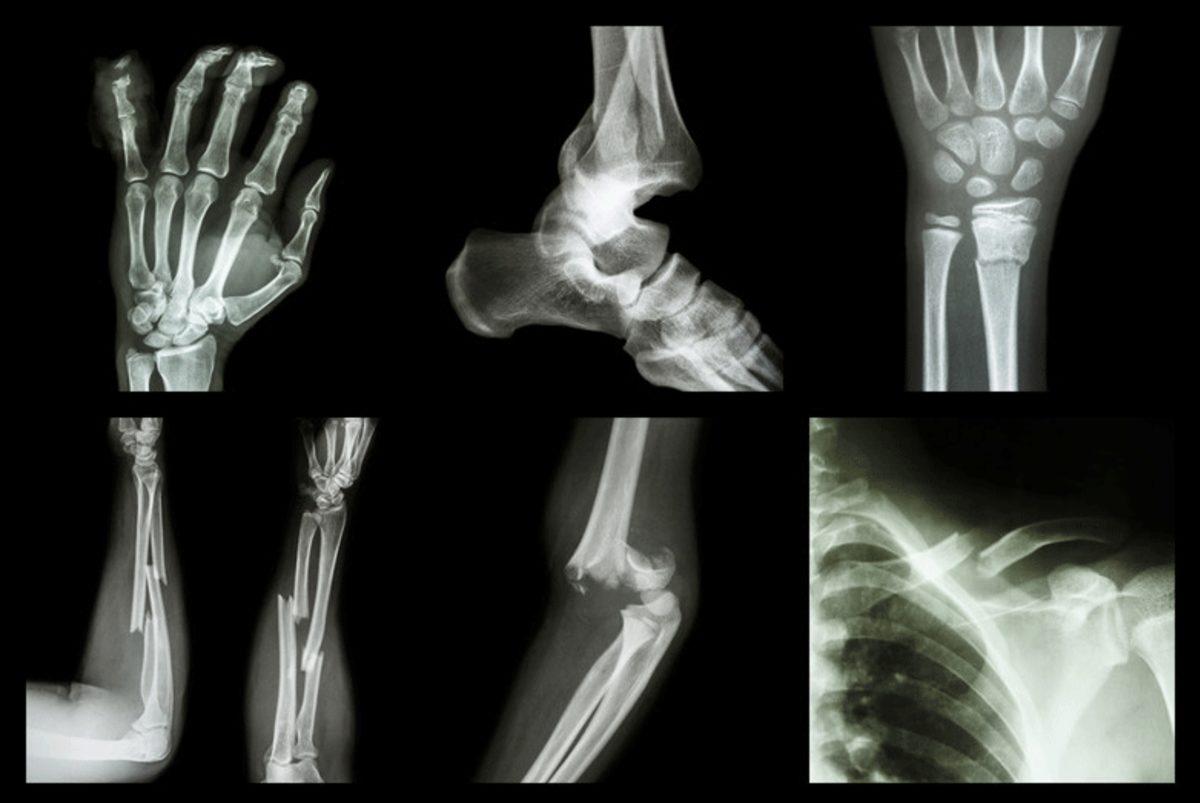

Bu her zaman için doğru değil. Vücudunuza aldığınız herhangi bir darbede kırığı tespit etmek için sorulan bu soru çoğu zaman kırığa işaret etse de bazen kırılan kemiği kımıldatabilmeniz mümkündür. Kırığın bilinen en büyük üç belirtisi şunlardır: Ağrı, şişme ve şekil bozukluğu.

Fazlasıyla yanlış ve tehlikeli bir düşünce daha. Kırığın çapı, herhangi bir tendon yırtığı olup olmadığı bilinmeden kaderine terk etmek oldukça yanlıştır. Nitekim parmak kırıklarının iyileşme süreci 4-6 hafta periyodundadır ve bu süreçte kötü açılardan oluşan kırıklar geri dönülemez yaralanmalara sebep olabilir.